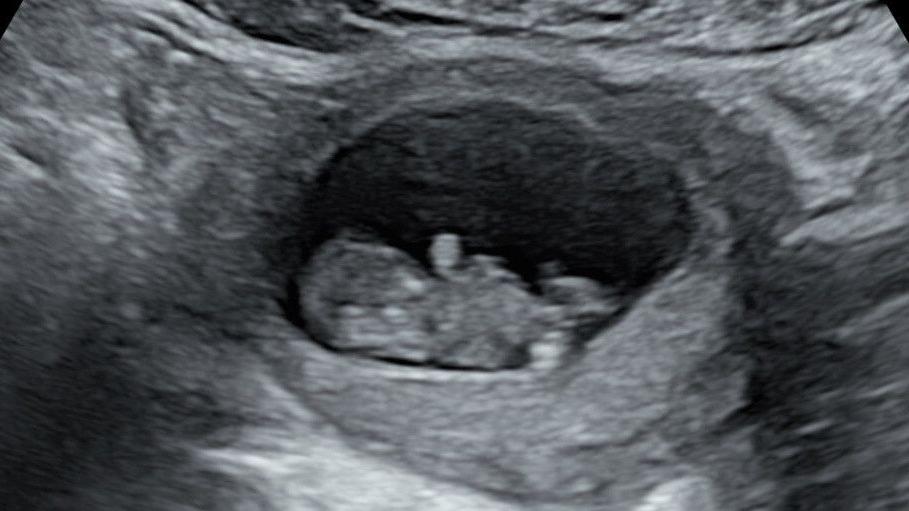

Imagem BBC Brasil

Um ultrassom do segundo bebê de Rhiannon Lawson, que foi diagnosticado com doença rara com 20 semanas Crédito: Arquivo pessoal/Rhiannon Lawson

Em outubro do ano passado, ela descobriu que estava grávida novamente e, desta vez, ficou mais tranquila com alguns exames iniciais.

Mas então veio o ultrassom de 20 semanas, que revelou que o bebê – que o casal chamou de Hudson – tinha uma forma grave de síndrome do coração esquerdo hipoplásico, uma doença cardíaca congênita rara em que o lado esquerdo do coração é subdesenvolvido.

"Não havia como seguir em frente", diz ela, e Hudson nasceu morto em março, com 22 semanas.